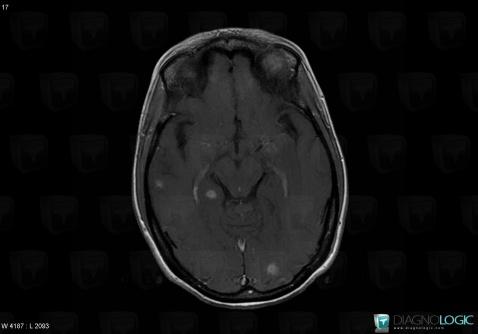

Toxoplasmosis, Posterior fossa, MRI

Here is the specific information in the key image above:

- Diagnosis Toxoplasmosis (link to Abscess), Location(s) Posterior fossa, with gamuts Multifocal infratentorial lesions